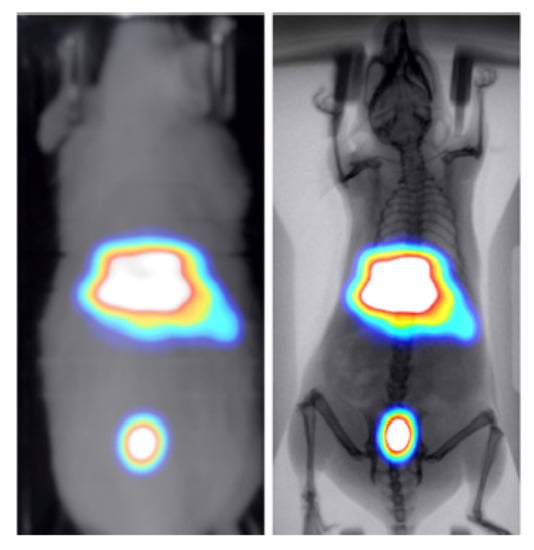

3.2. Animal Mapping during In Vivo Molecular Imaging Experiments